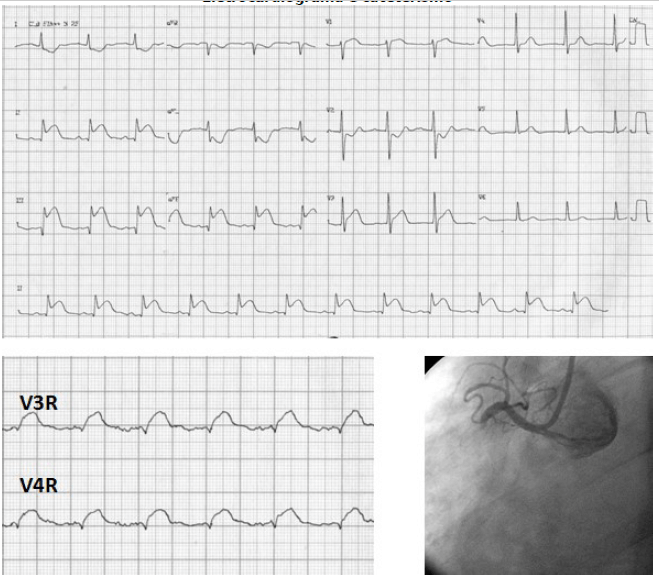

Paciente hipertensa e diabética deu entrada no ponto atendimento, apresentando dor torácica em aperto, associada a náuseas. No hospital, foi diagnosticado com síndrome coronariana aguda e levado ao cateterismo.

Eletrocardiograma e cateterismo

Em relação a paciente acima, qual droga deve ser evitadas nesse paciente: